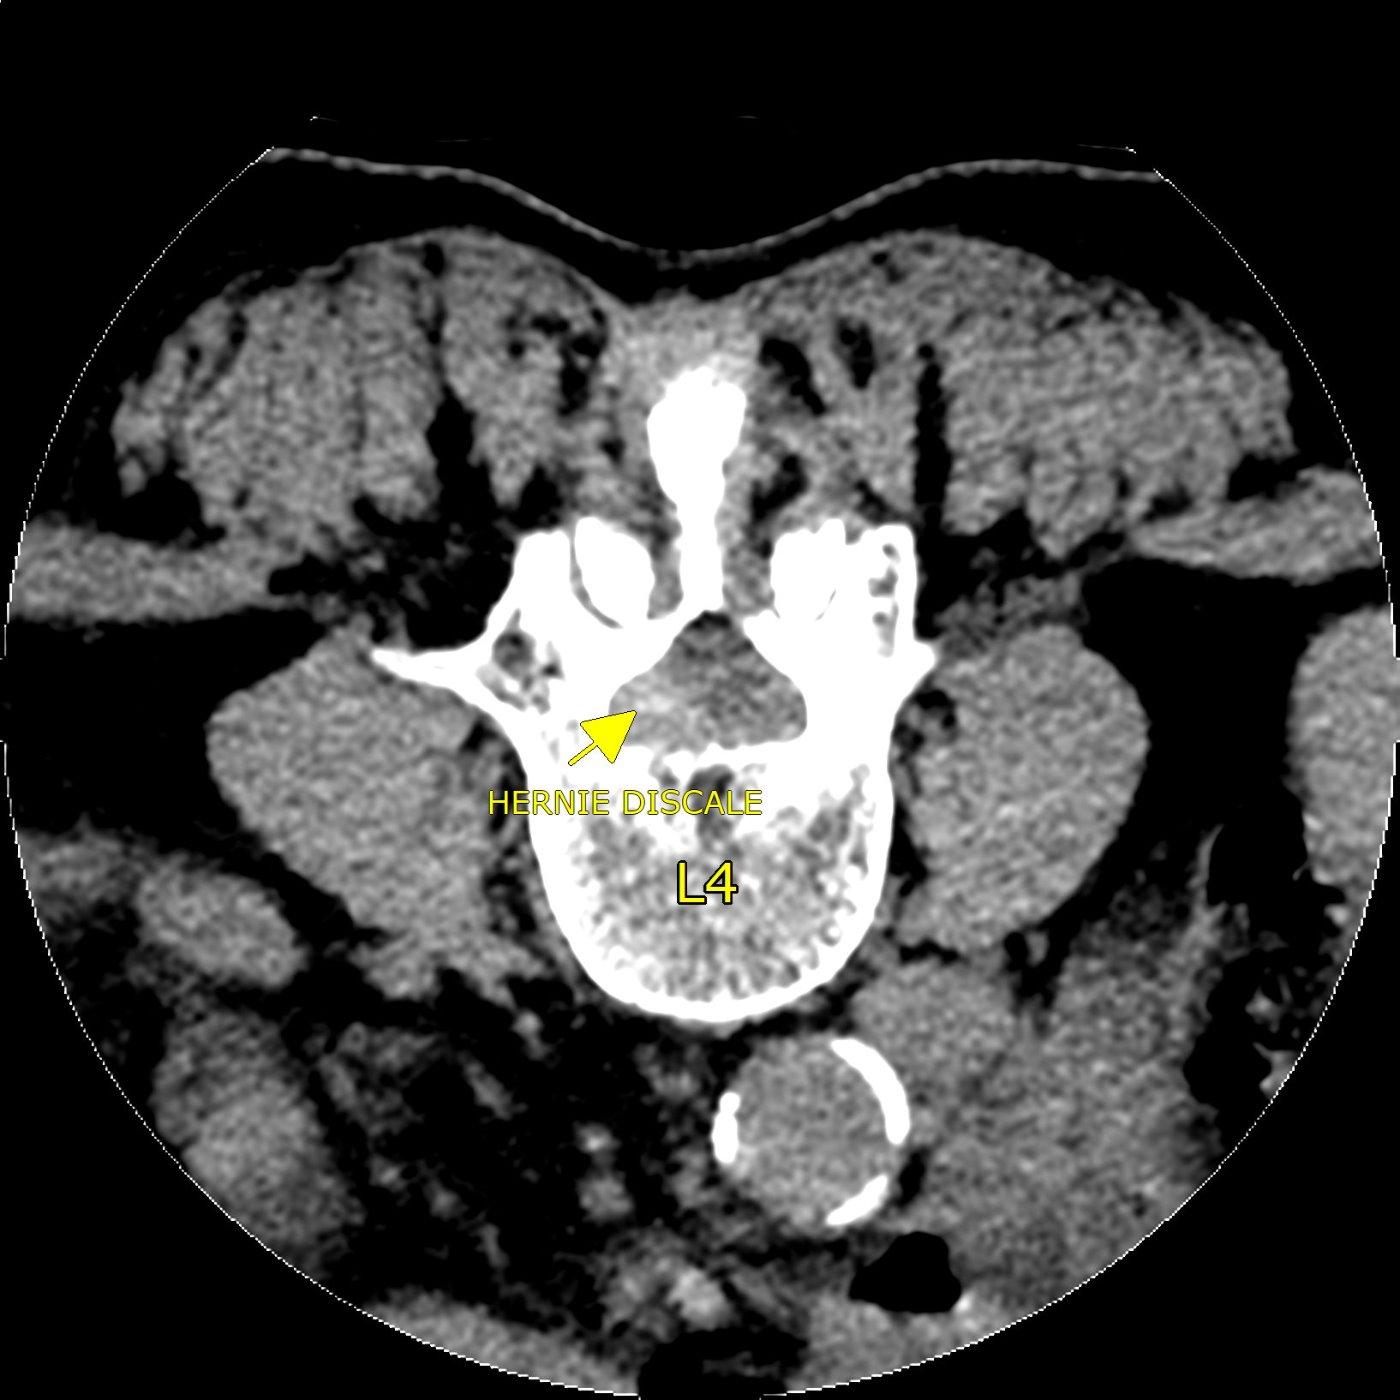

INFILTRATION LOMBAIRE POUR HERNIE DISCALE

la flèche jaune indique la présence d'une hernie discale au niveau de la 4è vertèbre lombaire, responsable d'une cruralgie

Lorsqu'une douleur de "sciatique" ou une cruralgie est provoquée par une hernie discale lombaire, et que la douleur résiste à un traitement médical maximal, le médecin peut proposer la réalisation d'une infiltration lombaire, c'est à dire une injection de corticoïdes dans l'espace épidural.

Nous réalisons cette procédure sous guidage radiographique ou scanner, patient allongé sur le ventre.

La durée de l'intervention est courte, une vingtaine de minutes en comptant l'installation. Après l'infiltration, le patient est installé en position semiallongeé dans une salle au calme.

Un repos doit être observé pendant les 48 heures suivant l'infiltration.

L'efficacité de l'injection s'installe dans les 8 à 15 jours qui suivent l'infiltration.